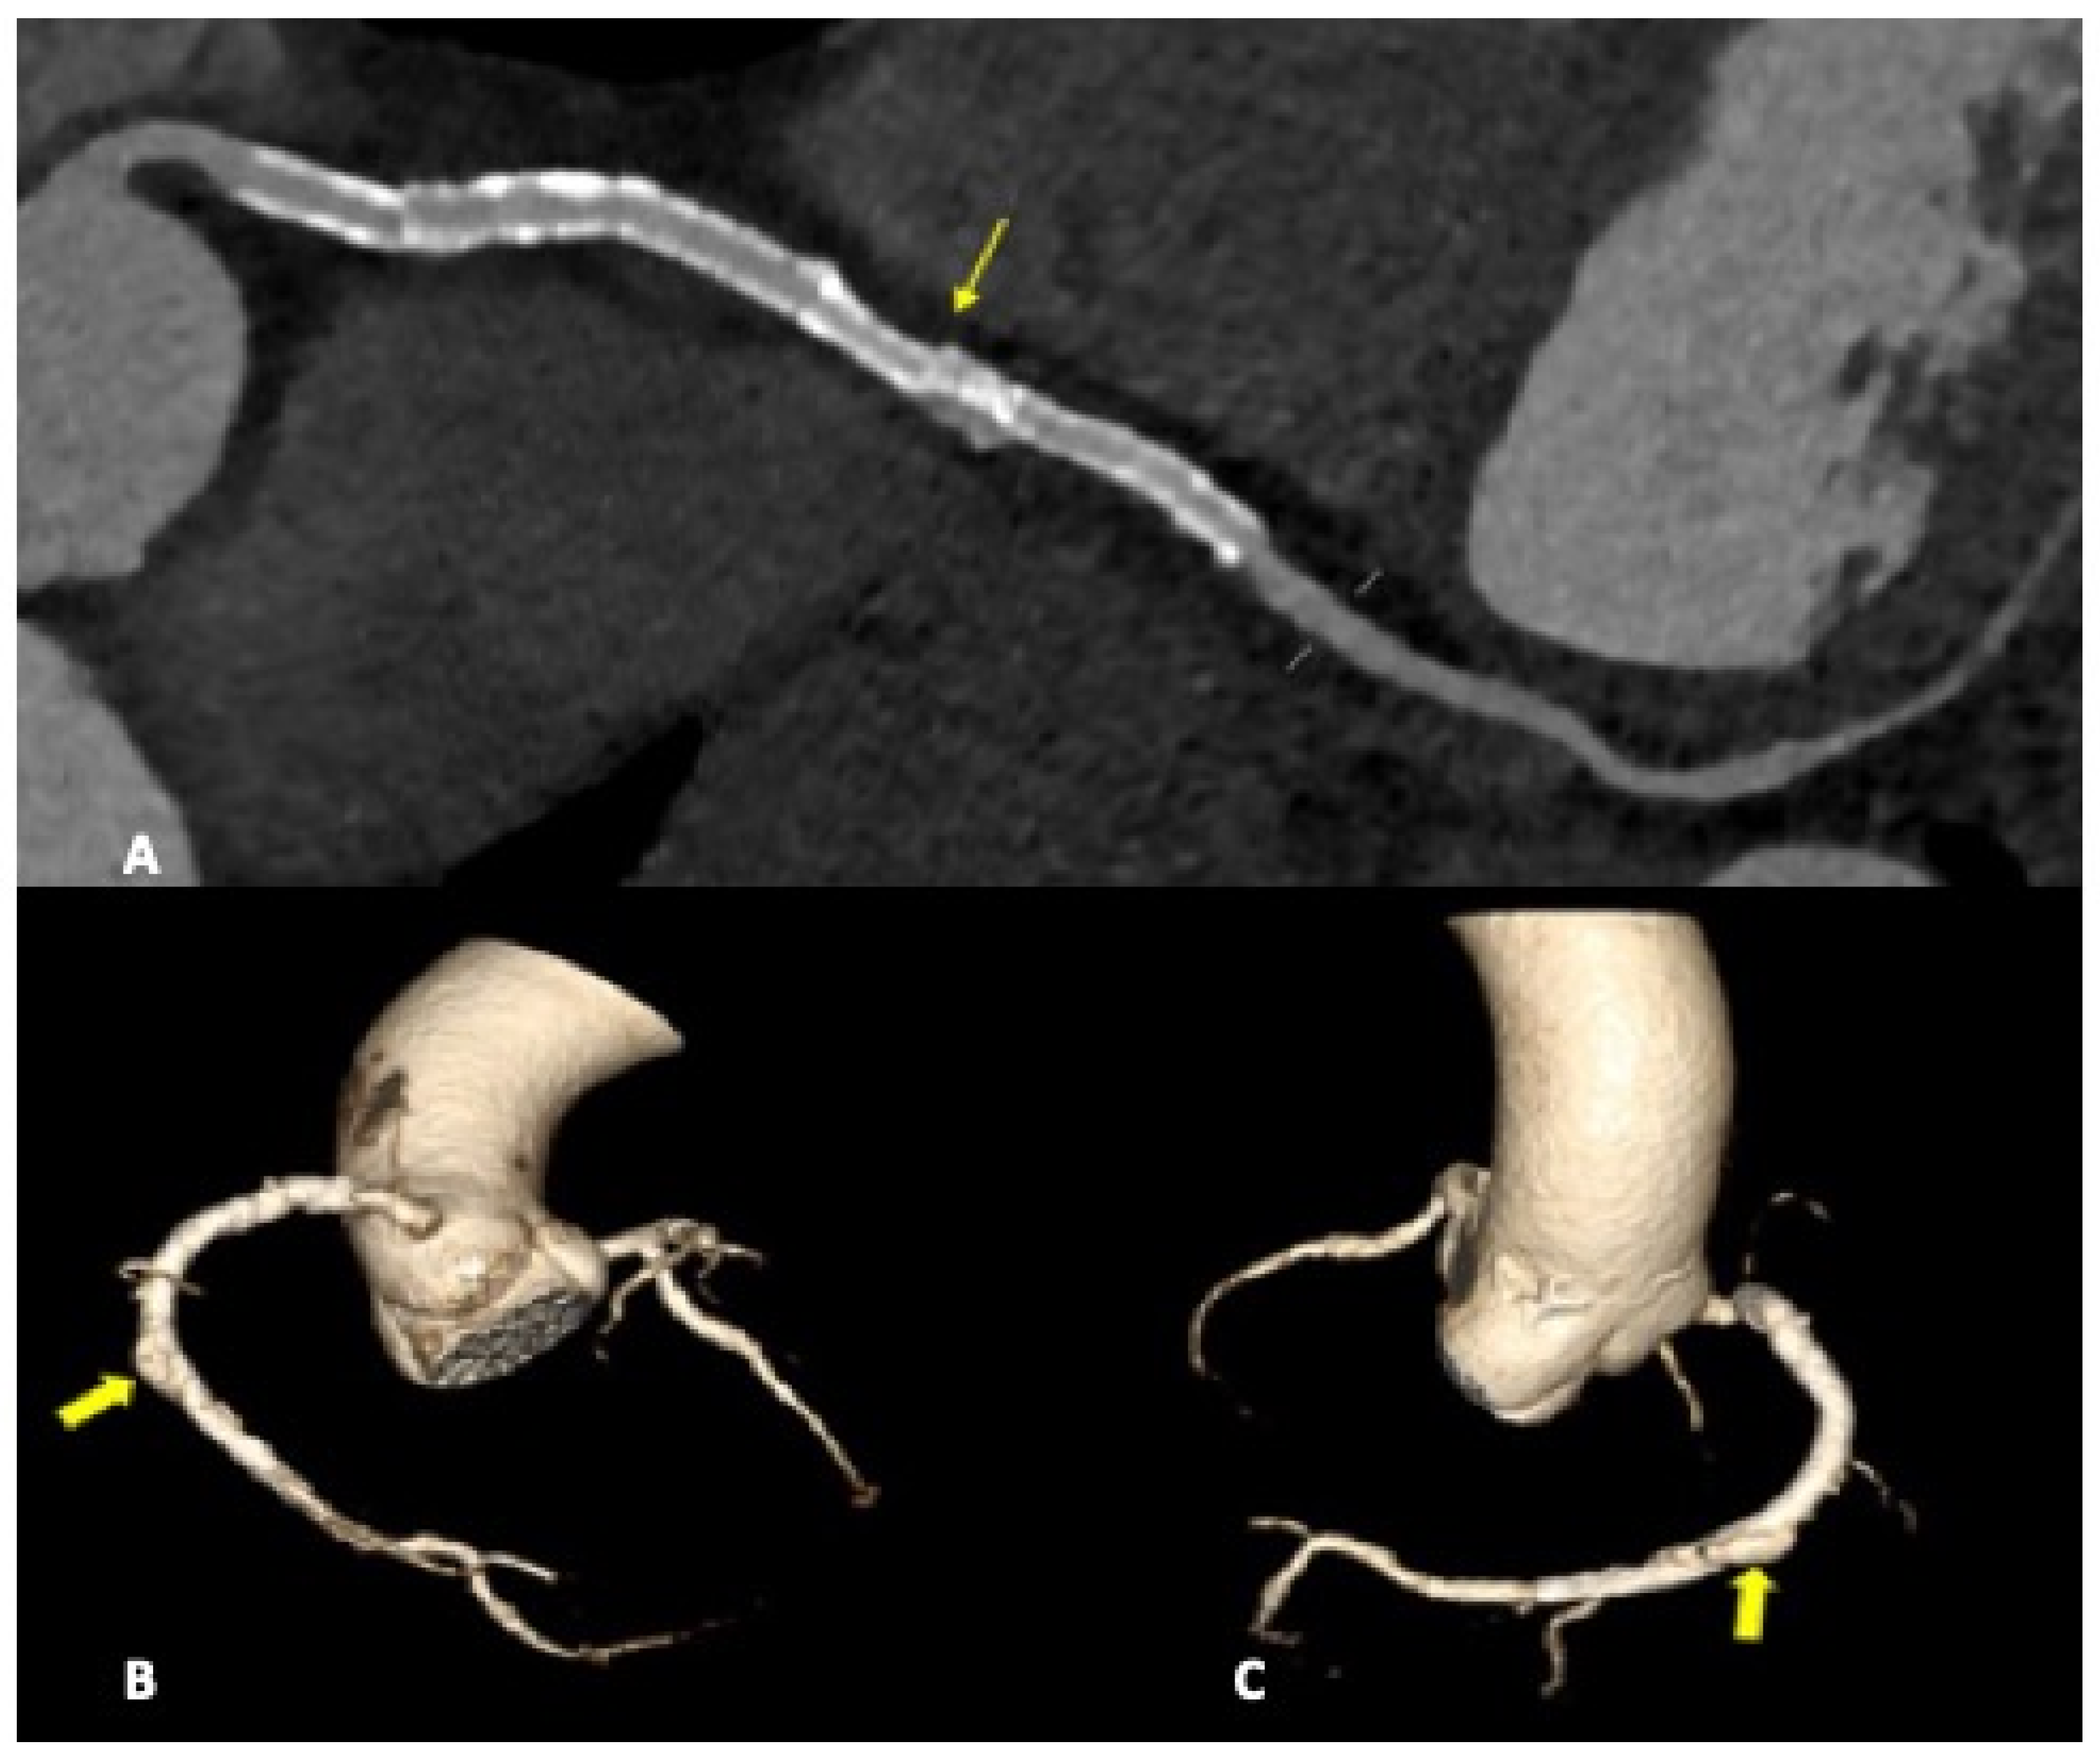

Among percutaneous coronary intervention (PCI) complications, coronary intimal dissection was found to be the most frequent event after PTCA (6/27 patients, 22.2%), associated with involvement of the ascending aorta (Figure 1). All coronary dissections encountered were noted in an emergency setting, and all of them involved the right coronary ostia, with a constant flap extension to the valsalva sinus and ascending aorta wall (less than 40 mm distance from the ostium).

Intimal dissection in the aortic or coronary wall during PCI is an infrequent complication characterized by the formation of a hematoma in the media and separation of the intimal layer, with compromise of the coronary blood flow. It can be explained either by direct trauma from the catheter tip or a vigorously expelled jet of contrast material from the catheter tip that abuts the wall of the coronary artery. Among risk factors that must be taken into account are female gender, mechanical trauma, technical factors such as the inappropriate positioning of the catheter tip in the coronary artery ostium, and overinflation of the angioplasty balloon. Ascending aortic dissection is more frequent during procedures involving RCA because of its smaller caliber and the hemodynamic force vector directed to the right convexity of the ascending aorta [20]. In our study, all cases of coronary artery dissection involved the RCA with the flap extension to the right valsalva sinus. CCTA can accurately define the aortic involvement guiding the correct management because limited aortic involvement may be treated by stenting the coronary dissection entry point, whereas extending aortic dissection distant from the coronary os may require surgical intervention [20]. The capability of CTA to precisely assess intimal flap extension and the presence or absence of intramural hematoma are fundamental to correct patient management. Moreover, a gated CTA scan is helpful for determining the coronary vessel patency impairment when present and consequently to establish the exact true and false lumen width.

Figure 1. CCTA, curved planar reconstruction: (A) ascending aorta dissection involvement (arrowhead); (B) RCA ostial dissection can be noted (arrow).

Figure 3. CCTA, a curved planar reconstruction of RCA (A) and volume-rendering reconstruction of coronary tree (B,C). A: multiple stents in RCA can be seen. The most distal stent is misaligned (light arrow), with vascular dilatation and endoleak in the same vascular tract. (B,C): medium-contrast extravasation outside the stent in the distal RCA determines a constrast sacciform collection outside the stent meshes as an endoleak type III formation (heavy arrows).